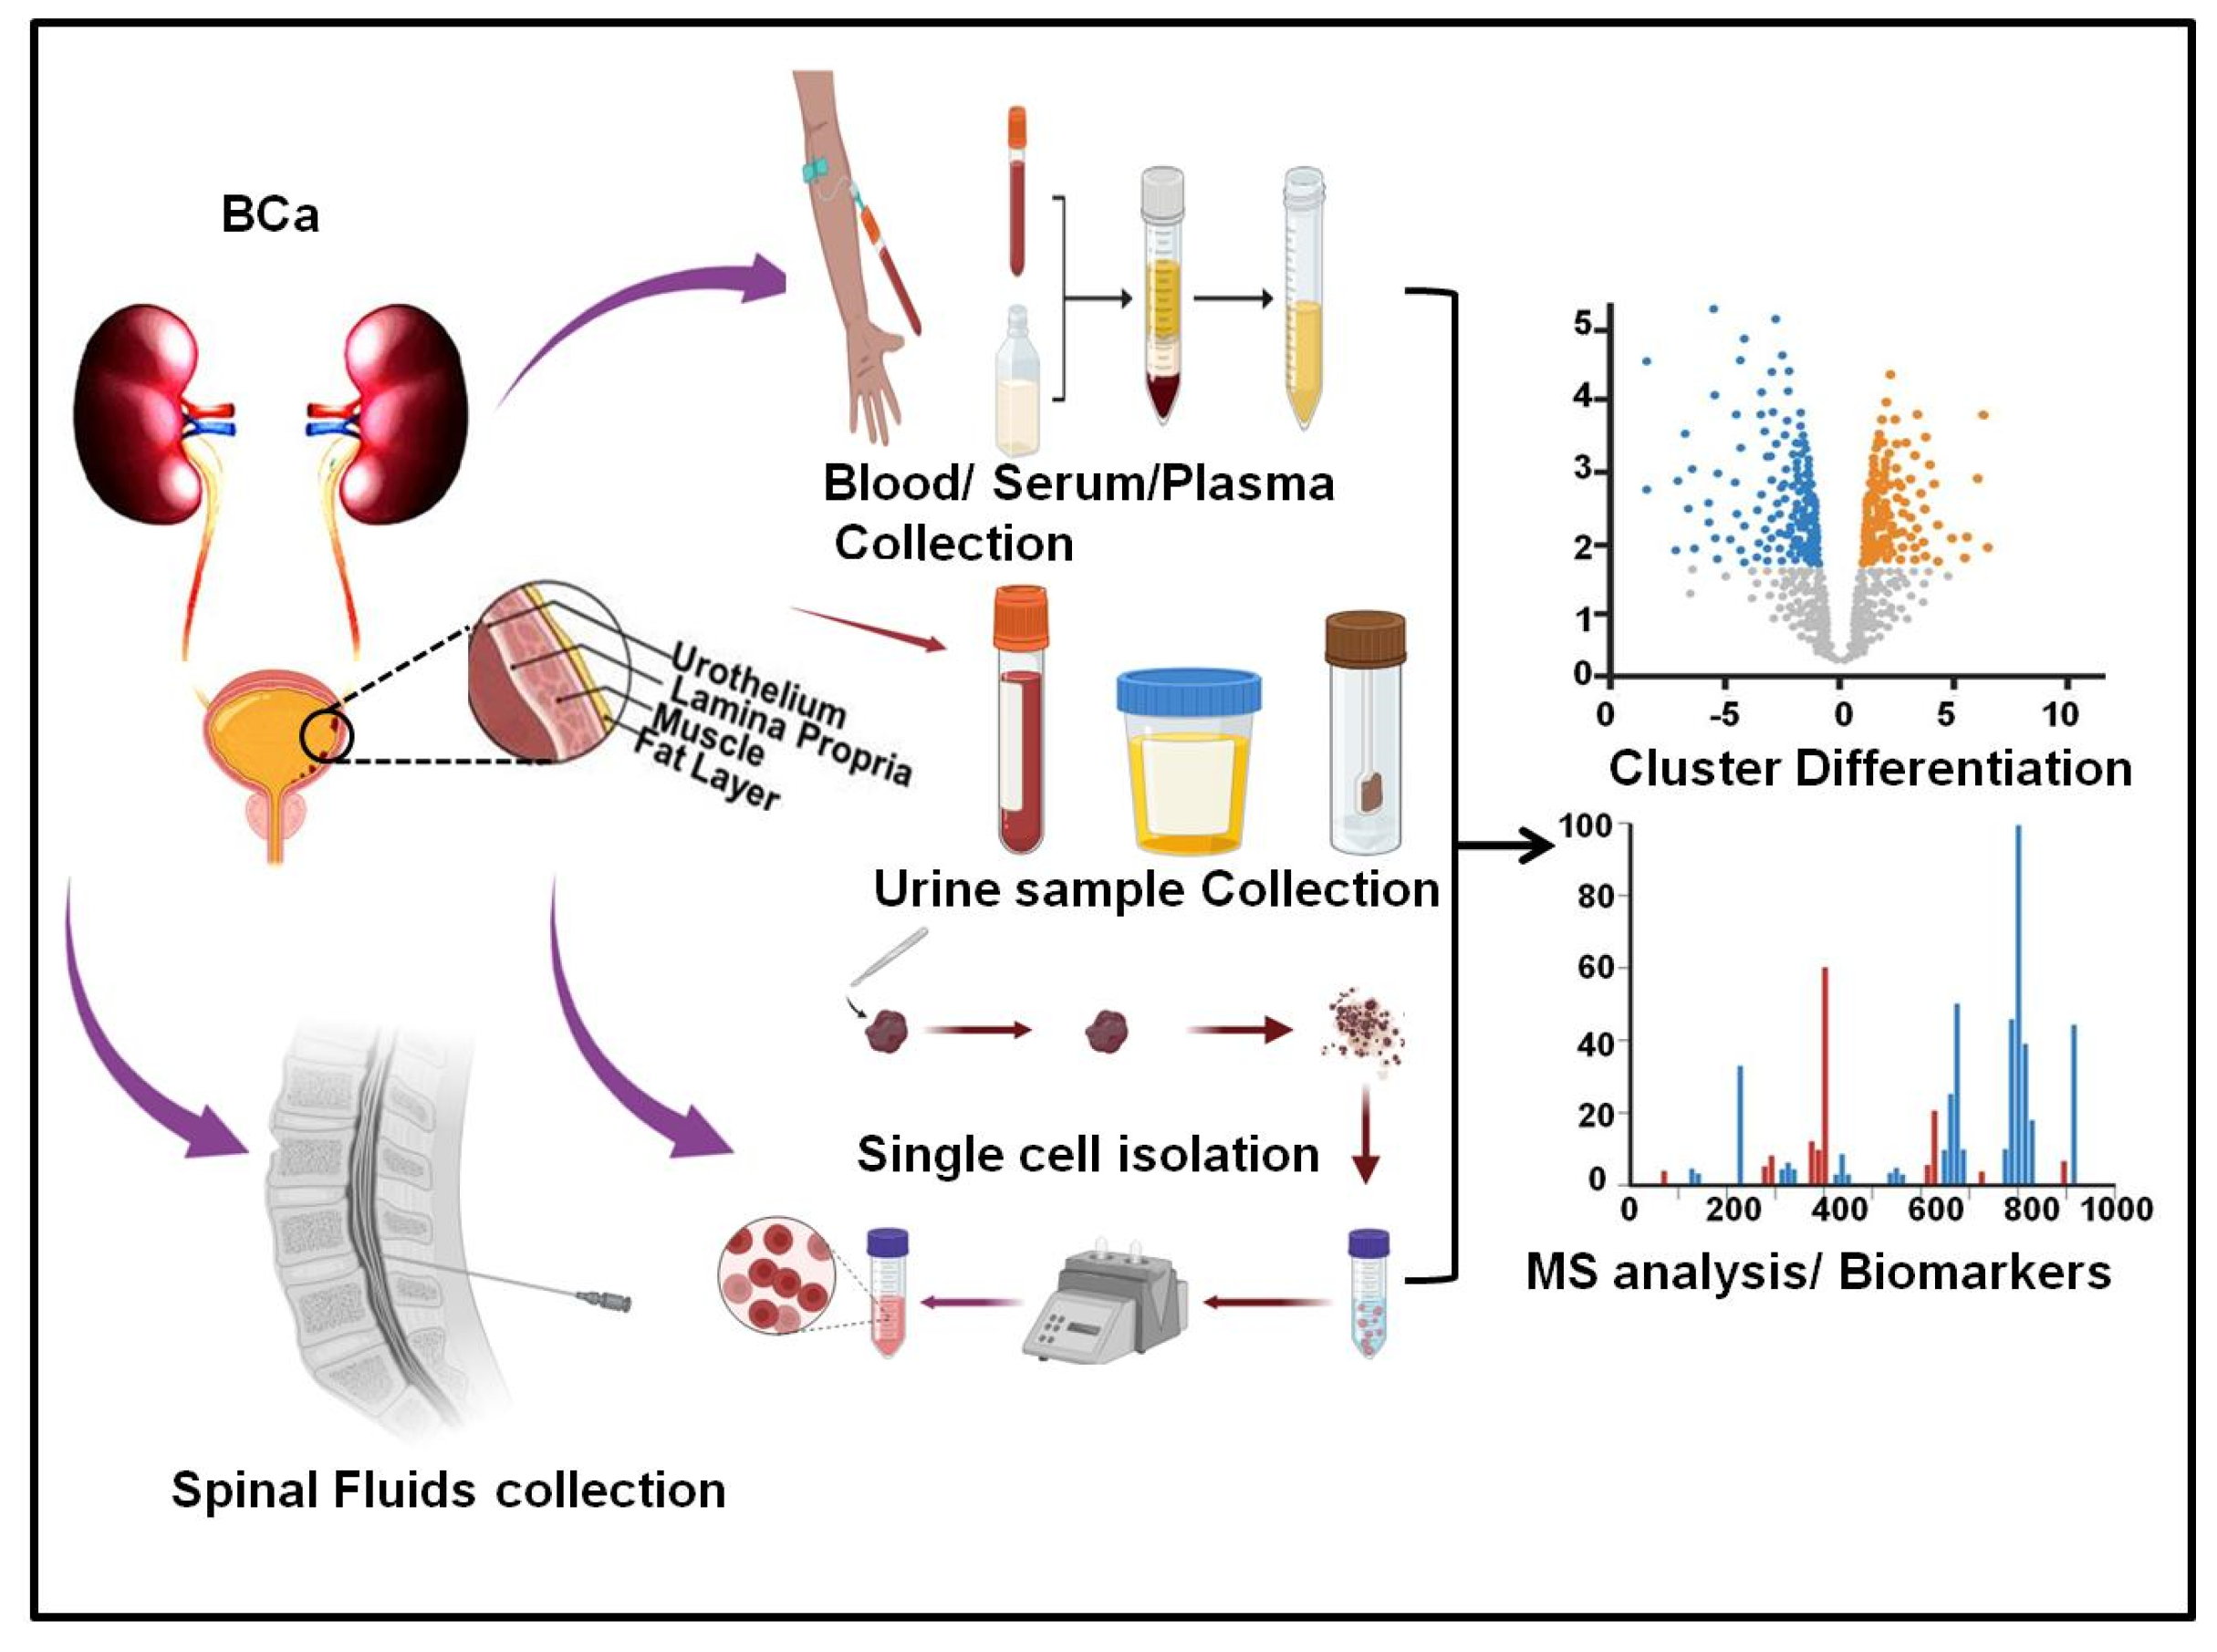

2.1. Serum Metabolic Analysis in Bladder Cancer

2.2. Urine Metabolic Analysis in Bladder Cancer

2.3. Tissue Metabolic Analysis in Bladder Cancer